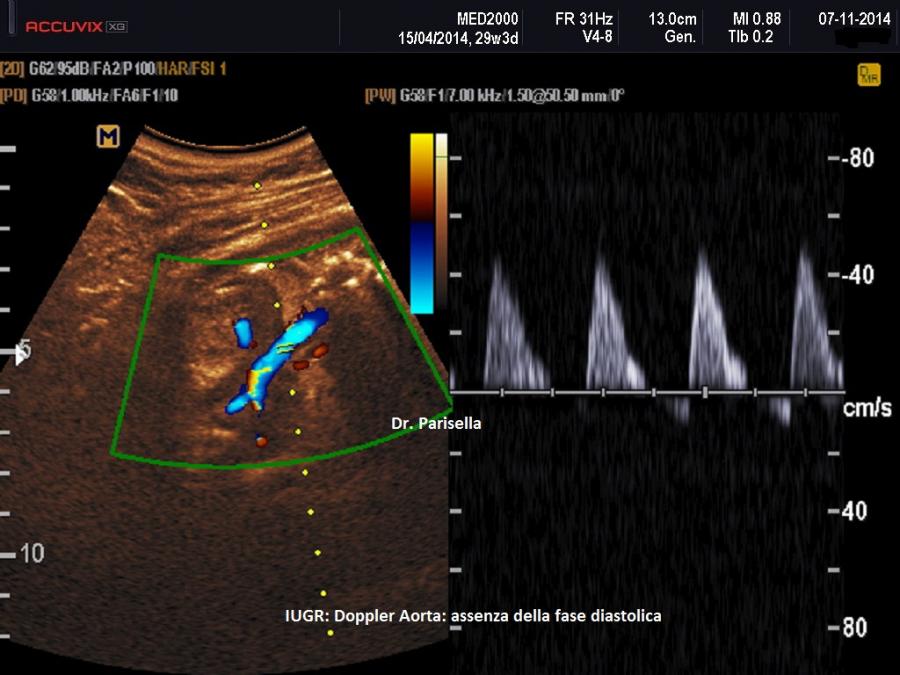

Aorta Fetale - L'indice di pulsatilità (PI) in aorta è anch’esso correlato alla prognosi fetale. Il flusso in aorta, dopo la 20a settimana di gestazione, è caratteristicamente un flusso ad alta resistenza con valori di P.I. attestati intorno a 2,0. Il flusso aortico viene studiato valutando la fase telediastolica EDF (end diastolic flow): in condizioni patologiche la EDF può scomparire (EDF 0) o essere negativa (EDF -). In presenza di una condizione di ipossia cronica con iposviluppo asimmetrico del feto si ha un aumento del P.I. fino ad arrivare all'assenza della fase diastolica (EDF 0) ed in seguito, col perdurare della condizione ipossica, si ha l'inversione del flusso telediastolico in aorta discendente (EDF -).

MANAGEMENT

Monitoraggio e Timing del parto nei feti FGR cambiano a seconda dell’epoca gestazionale distinguendosi tre fasce di età gestazionale: fino a 26 settimane, da 26 a 32 settimane e oltre le 32 settimane (RCOG, 2014; Pilloni E et al., 2020). La valutazione ecografica si basa su: biometria, quantità di liquido amniotico, flussimetria Doppler delle arterie ombelicali, del dotto venoso di Aranzio, dell'aorta fetale e delle arterie cerebrali medie.